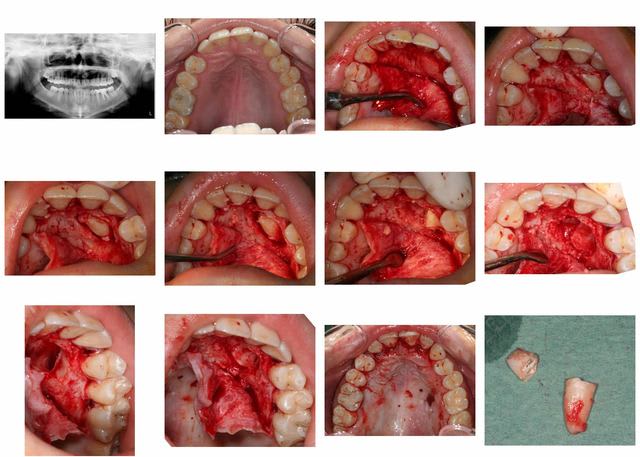

canine incluse

en dehors de ça, très belle chirurgie

> en dehors de ça, très belle chirurgie

Très joli mac et merci pour la belle iconographie!

Enfin, quel matéirel affectionnes-tu pour ce genre de chir? quelles sutures? quelles suites postop?

une lame 15, un décolleur, une fraise à os, un élevateur et du fil c'est tout.

points simples entre chaque dent.